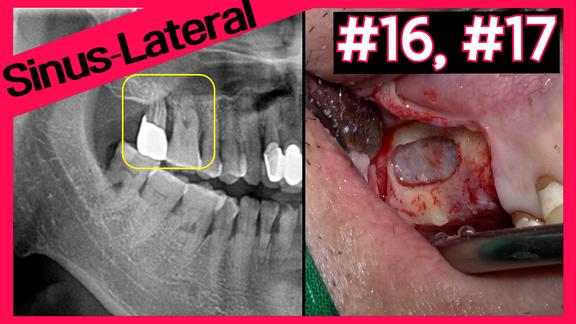

#15 Early implant placement with sinus lift with CAS KIT ...

Online Surgery

Views 545